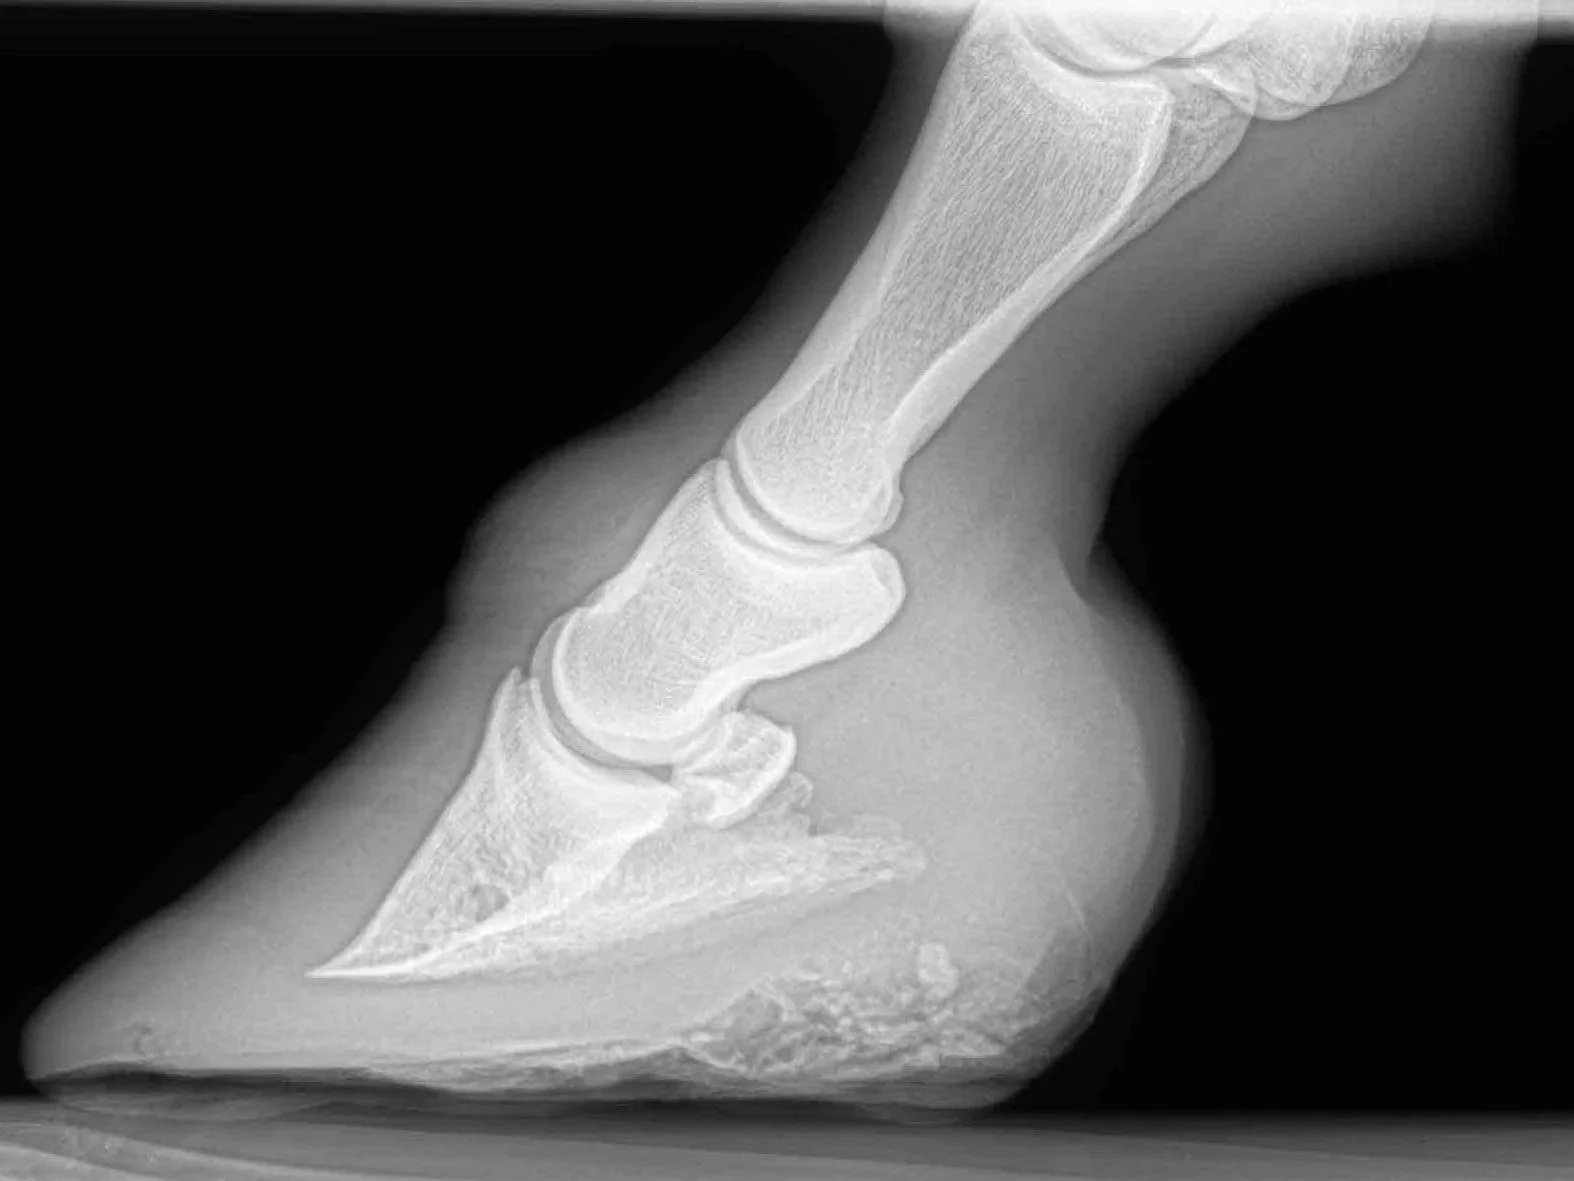

Vi undersöker hästar som visar problem i sitt rörelsesystemet . Vi har hjälp genom Röntgen och Ultraljud som bildgivande diagnostik.

• Röntgen